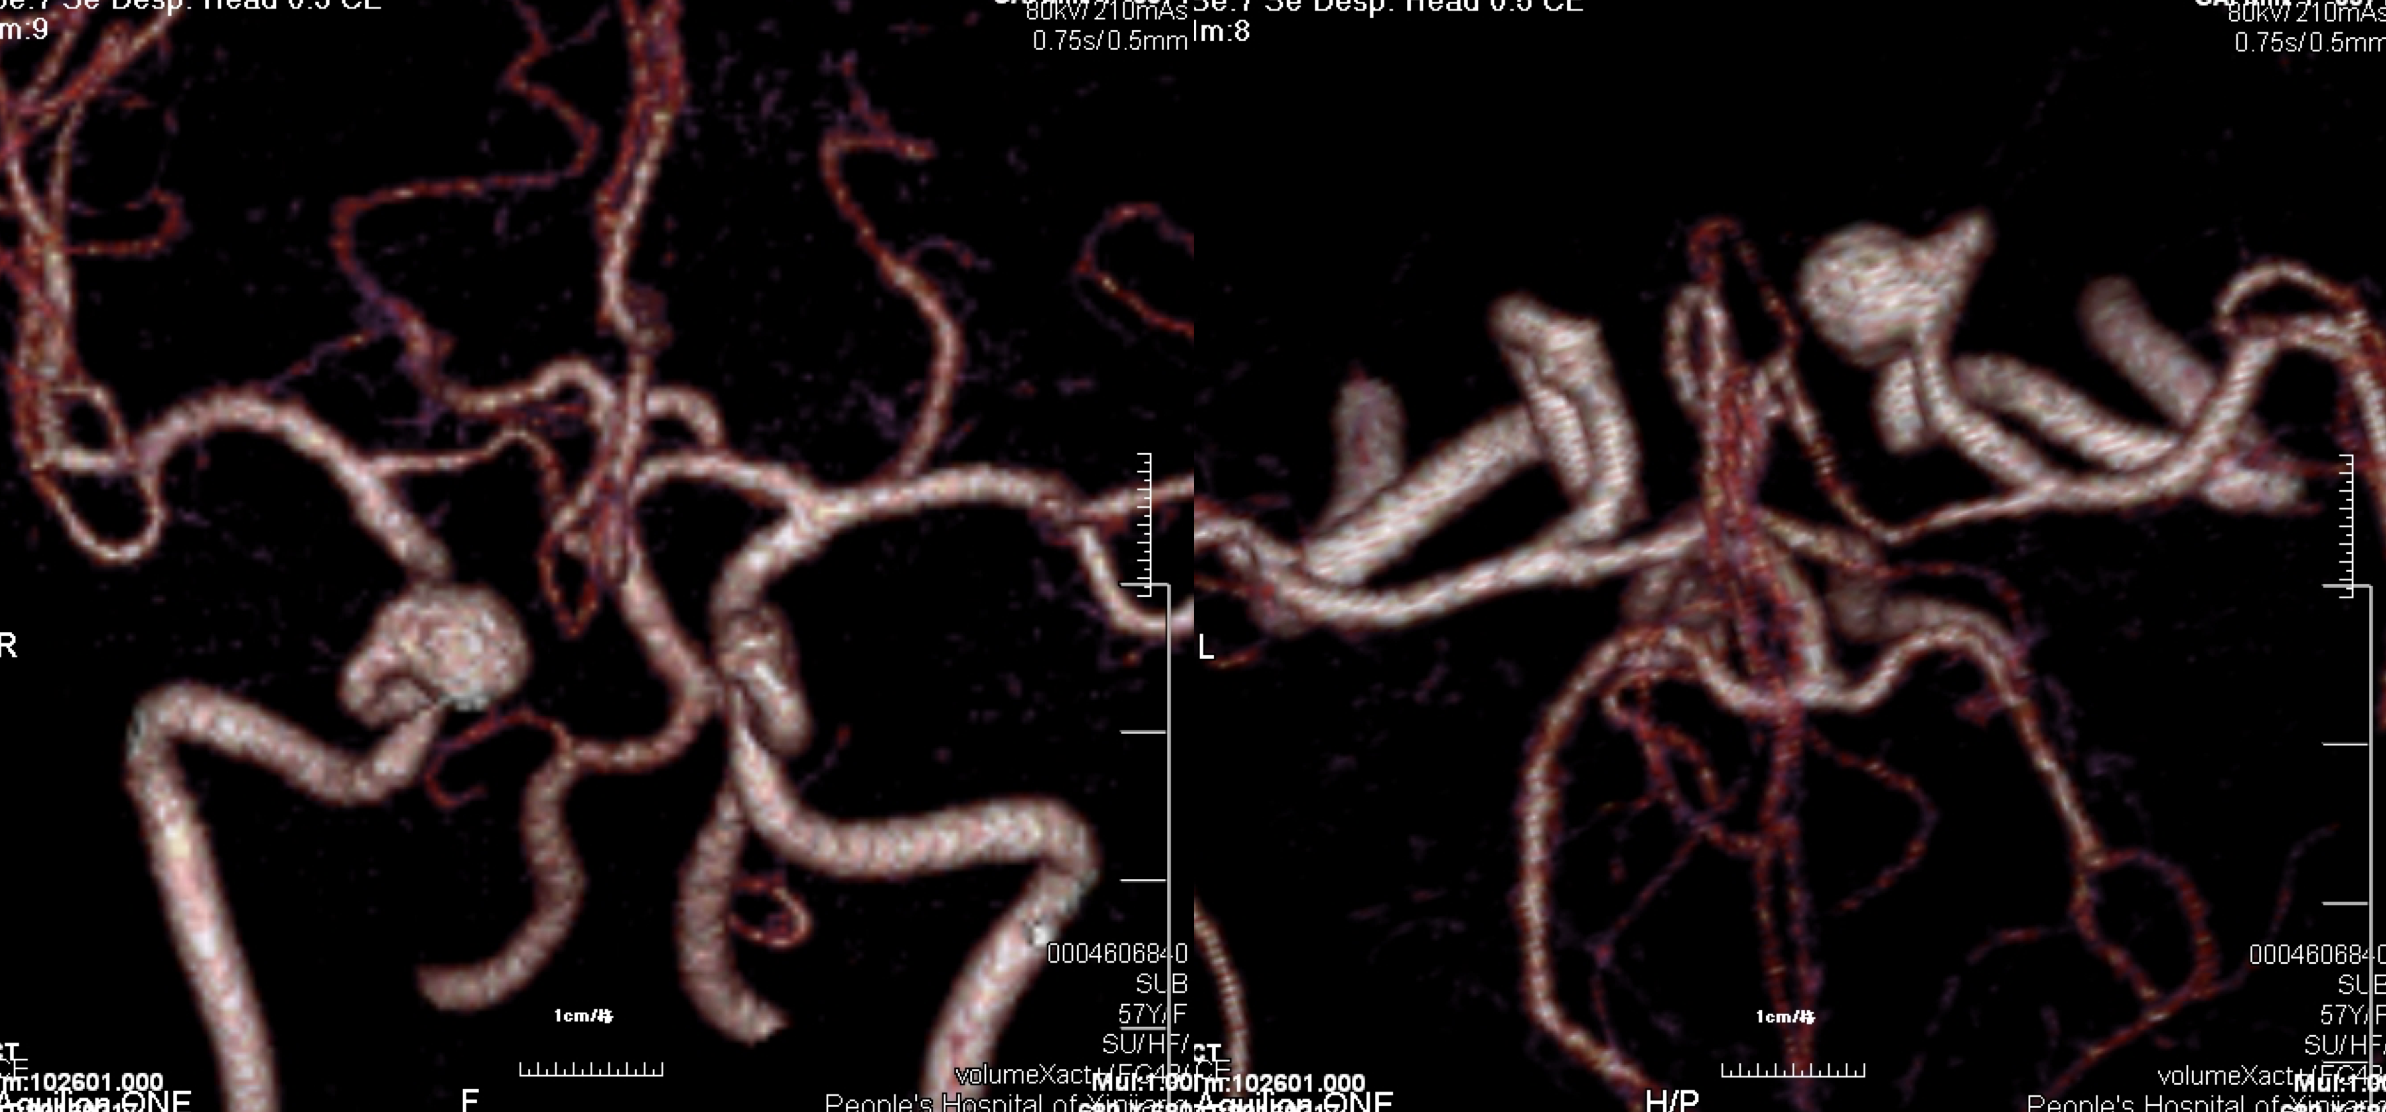

头颅CTA: 右侧眼动脉段动脉瘤。